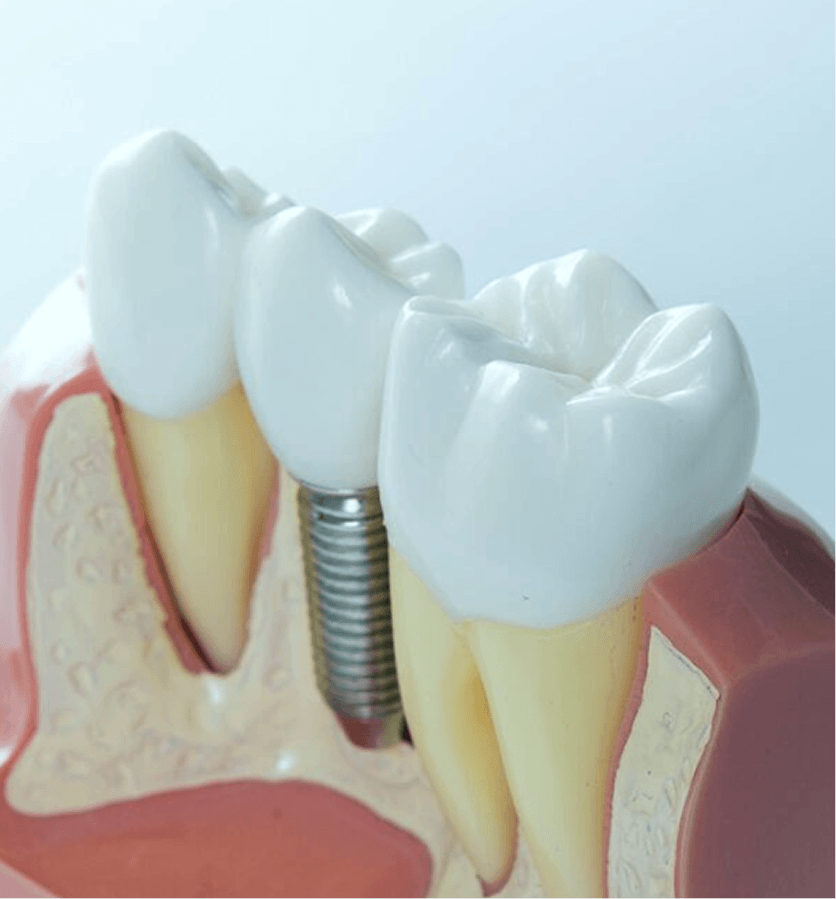

當牙齒缺失時,不僅影響外觀,更會導致鄰近牙齒移位及牙槽骨萎縮。

人工植牙是目前公認最能還原真牙功能的方案:

恢復咀嚼能力

預防牙齒走位

不損鄰牙

自然美觀

待植體與牙骨癒合後,再安裝個人化陶瓷牙冠。